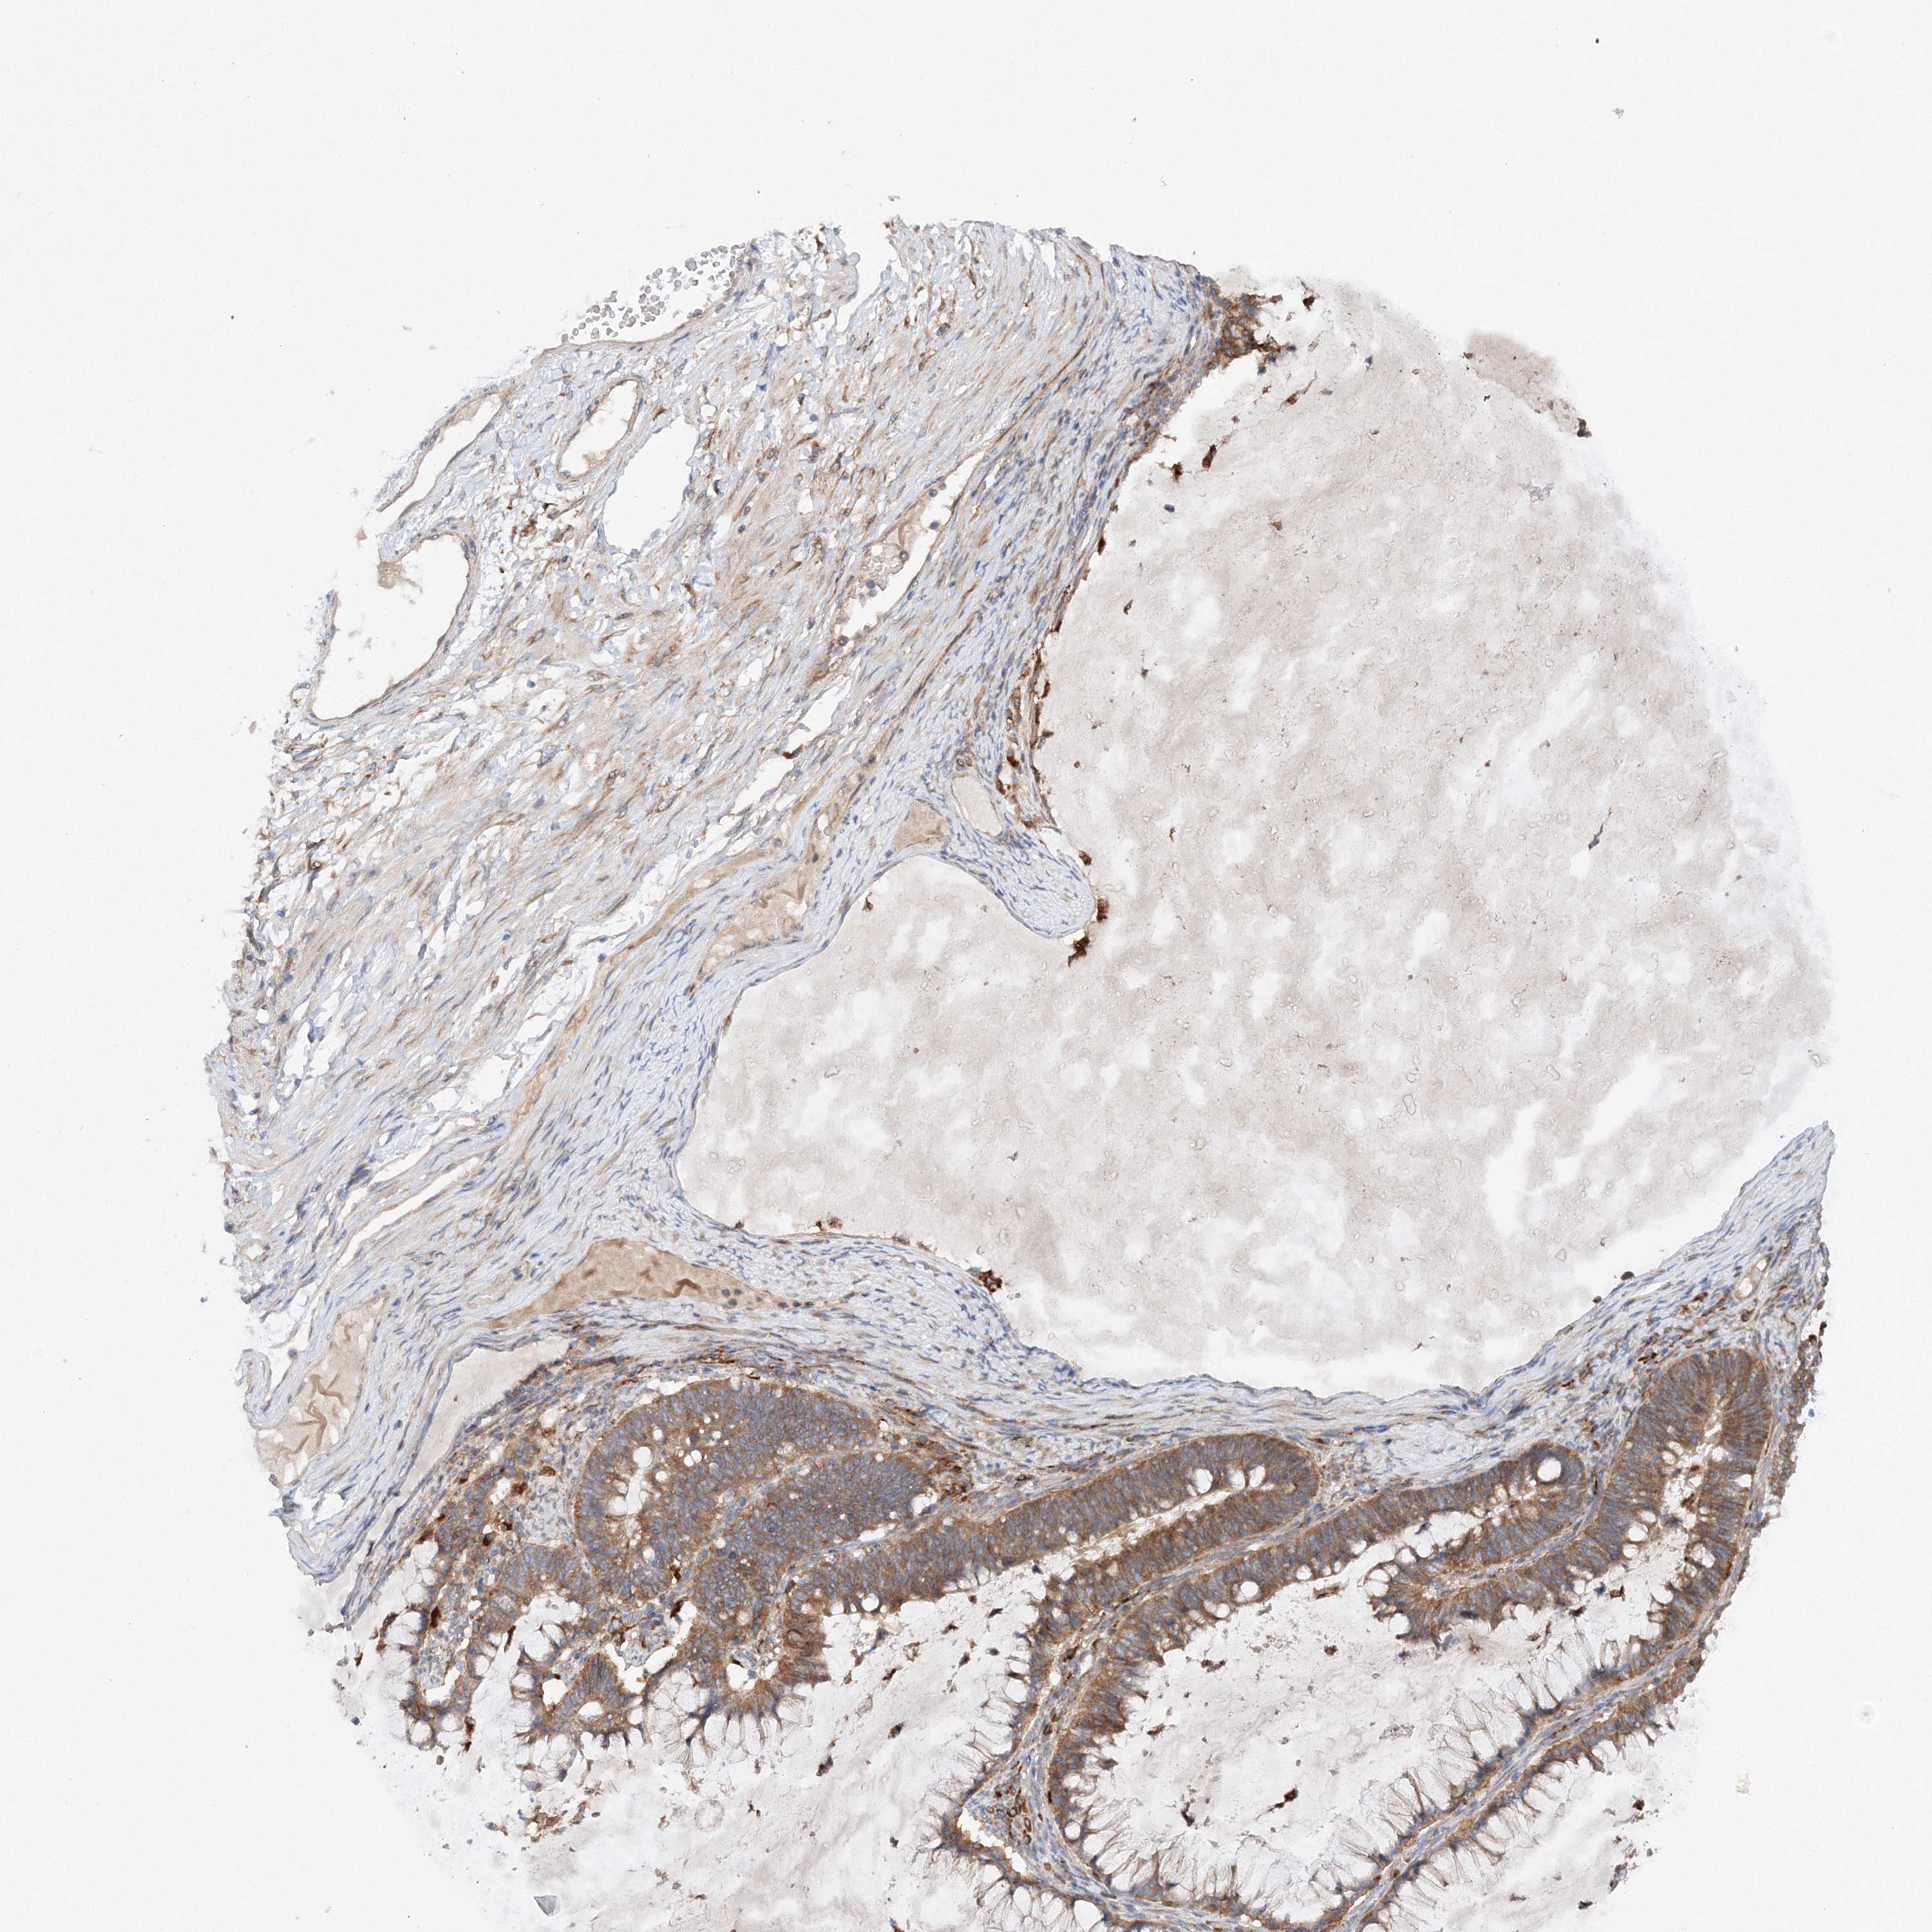

OVARIAN CANCER - Protein expressioni

A mouse-over function shows sample information and annotation data. Click on an image to view it in a full screen mode. Samples can be filtered based on level of antibody staining by selecting one or several of the following categories: high, medium, low and not detected. The assay and annotation is described here.

Note that samples used for immunohistochemistry by the Human Protein Atlas do not correspond to samples in the TCGA dataset.

Antibody stainingi

Antibody staining in the annotated cell types in the current human tissue is reported as not detected, low, medium, or high, based on conventional immunohistochemistry profiling in selected tissues. This score is based on the combination of the staining intensity and fraction of stained cells.

Each image is clickable and will lead to virtual microscopy that enables deeper exploration of all samples and also displays staining intensity scores, fraction scores and subcellular localization as well as patient and tissue information for each sample.

Antibody HPA035937

Staining

High

Medium

Low

Not detected

Intensity

Strong

Moderate

Weak

Negative

Quantity

>75%

75%-25%

<25%

None

Location

Nuclear

Cytoplasmic/membranous

Cytoplasmic/membranous,nuclear

Cystadenocarcinoma, serous, NOS

Carcinoma, endometroid

Cystadenocarcinoma, mucinous, NOS

Carcinoma, NOS